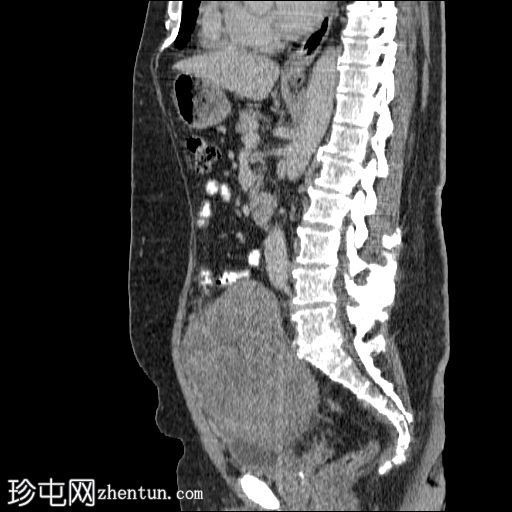

冠状位增强扫描(门静脉期)

2.jpg

盆腔内可见一大小为12 x 17 cm的边界清晰的异质性软组织肿块,向下延伸至下腹部。肿块内未见钙化或脂肪密度影。肿块向下推挤膀胱,并牵拉周围肠袢,但无放射学侵犯证据。未见明显淋巴结肿大、腹水或气腹。未见肺部或骨骼局灶性病变。肝脏可见数个小的单纯性囊肿。患者存在少量Bosniak I型肾囊肿,双侧肾盂肾盏系统饱满。曾行胆囊切除术。